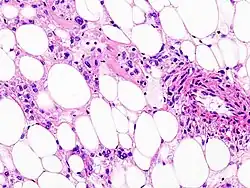

Histopathologic image of renal angiomyolipoma. Nephrectomy specimen. H&E stain.

PECs consist of perivascular epithelioid cells with a clear/granular cytoplasm and central round nucleus without prominent nucleoli.